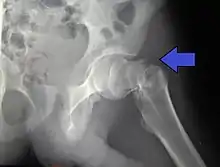

Nonunion, failure of the fracture to heal, is common in fractures of the neck of the femur, but much more rare with other types of hip fracture. Avascular necrosis of the femoral head occurs frequently (20%) in intracapsular hip fractures, because the blood supply is interrupted.[5]

X-rays of the affected hip usually make the diagnosis obvious; AP (anteroposterior) and lateral views should be obtained.